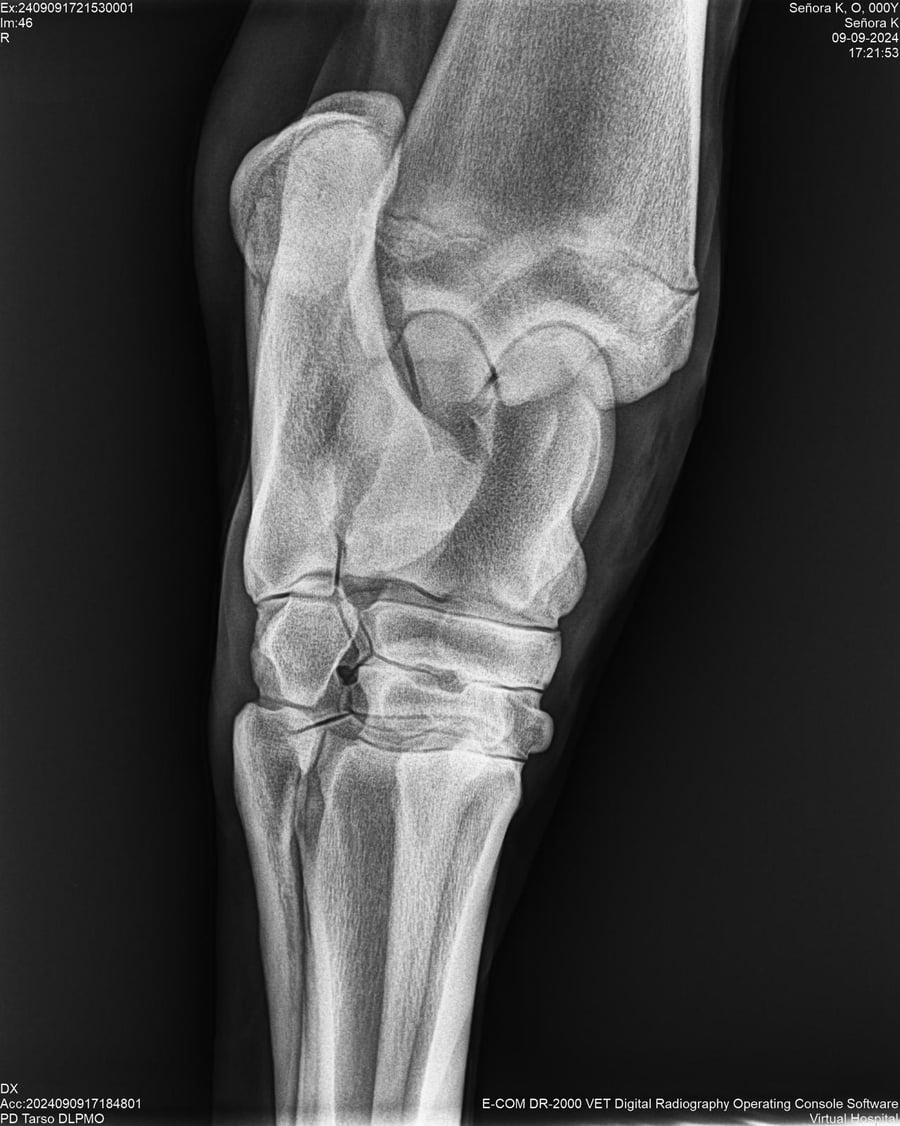

LOTE 44, SEÑORA K

Identificador: #291147-

Generacion 2022